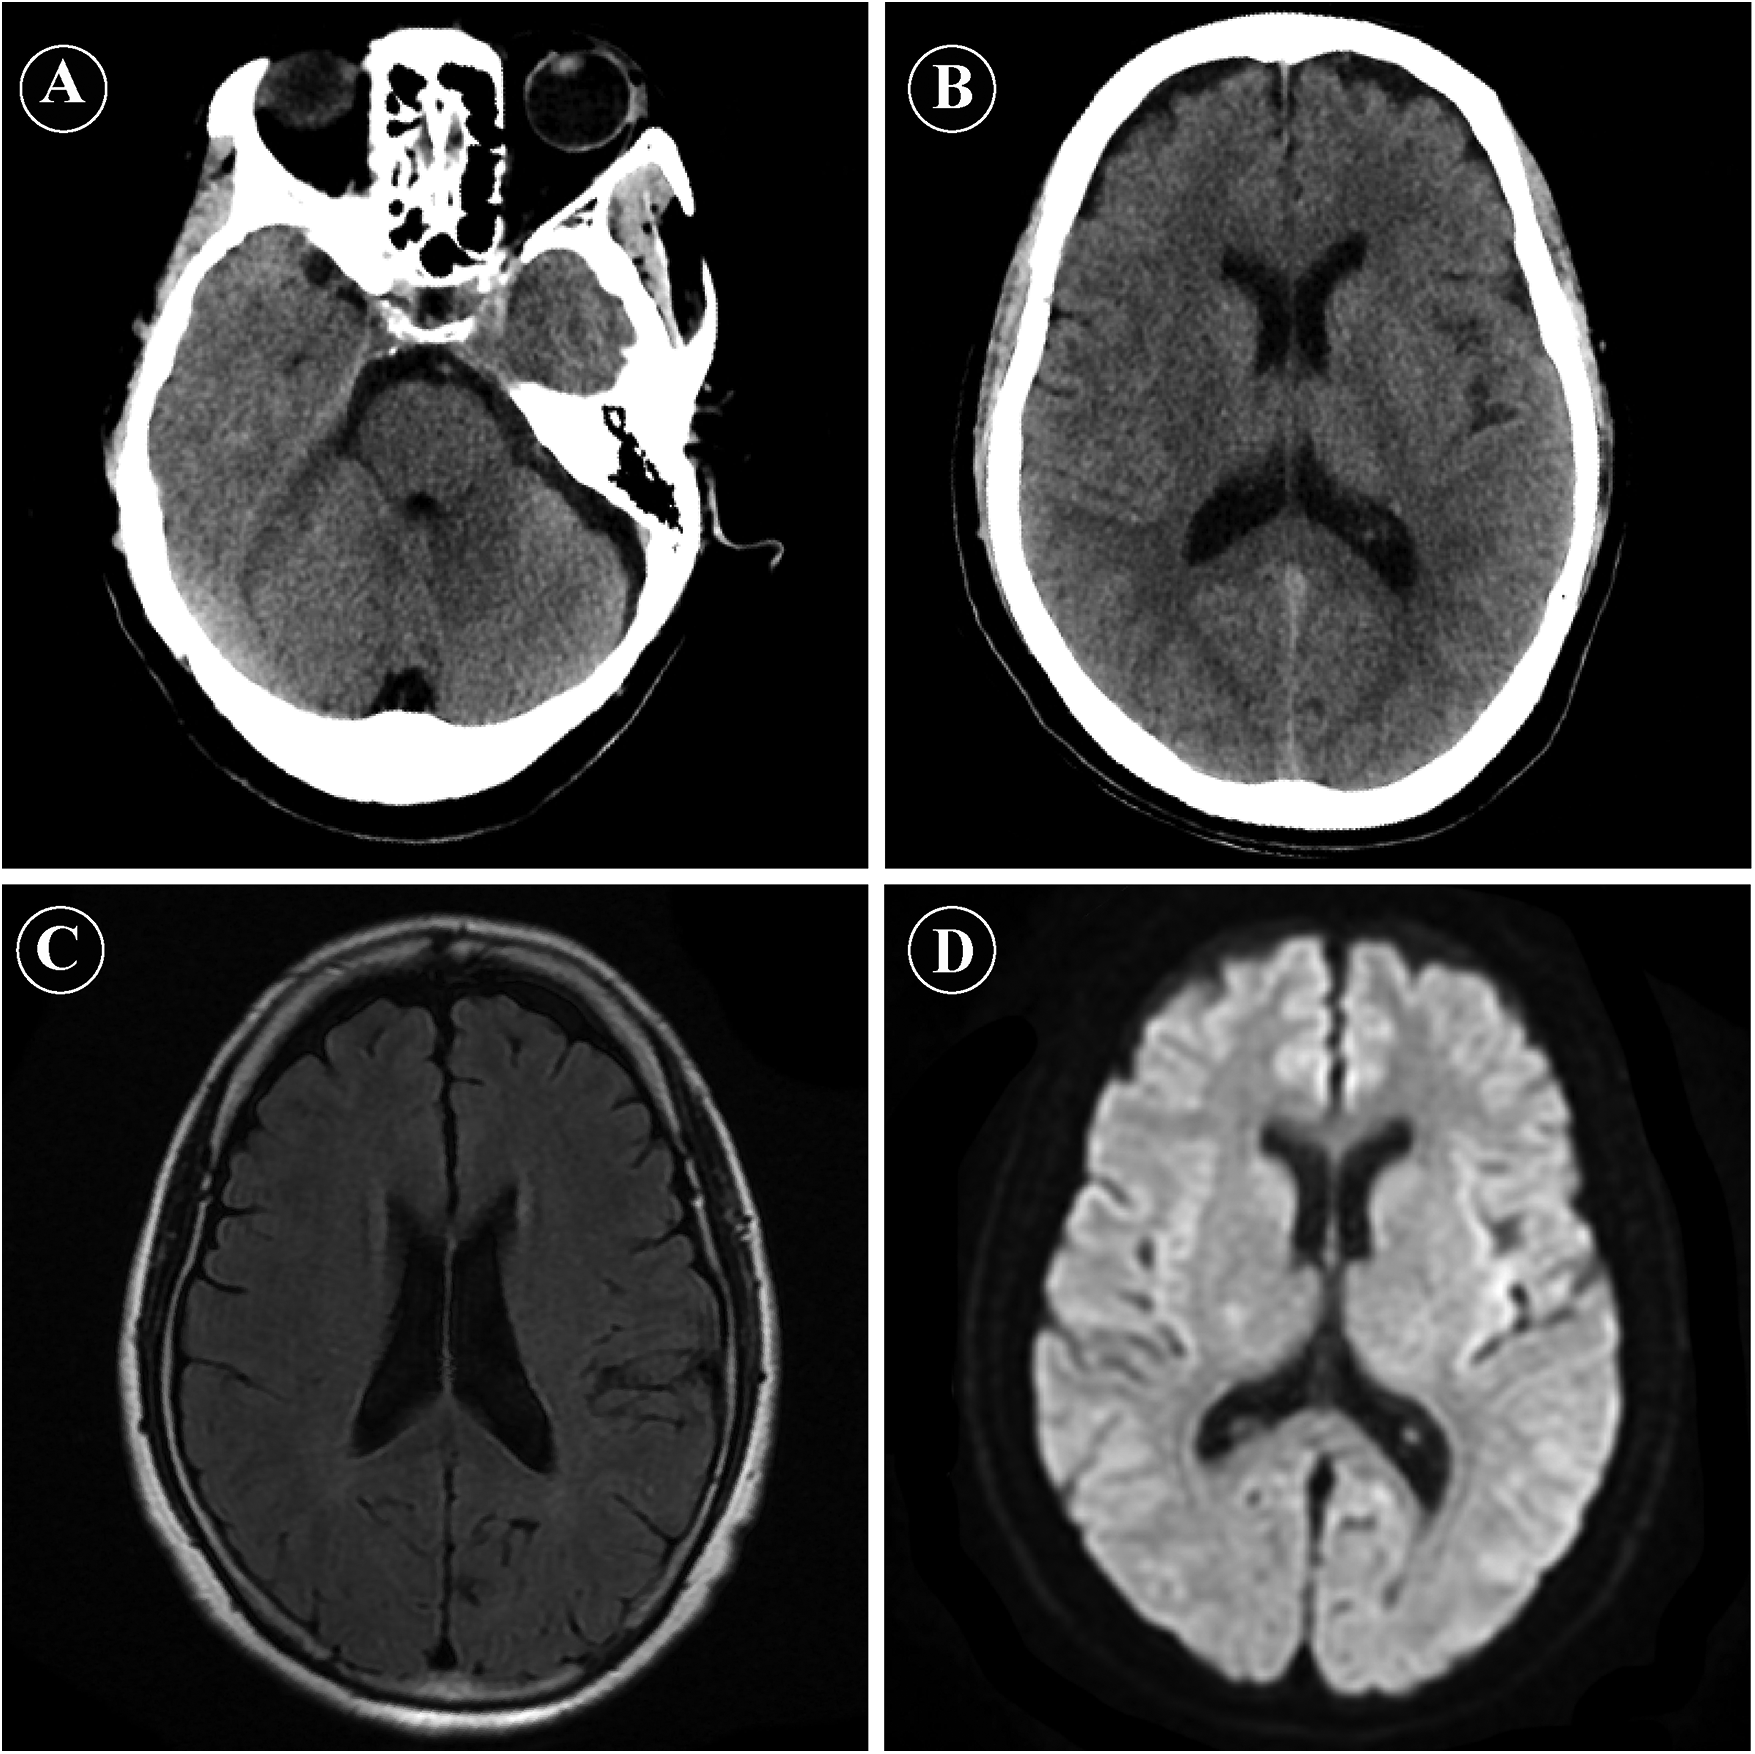

Approximately 10 min after completion of the procedure, the patient developed rapidly progressive bilateral visual loss, which progressed to complete blindness within several minutes. She also reported dizziness but denied limb weakness, speech difficulties, or seizures. On examination, she was alert and oriented, with intact pupillary light reflexes and no focal neurological deficits. Funduscopic examination was normal. Cranial CT and MRI (Figure 1) were performed approximately 8 min after symptom onset and demonstrated no evidence of intracranial hemorrhage, acute ischemic lesions, or abnormal signal changes in the occipital lobes. Given the close temporal relationship with contrast administration and the exclusion of other causes, a diagnosis of contrast-induced transient cortical blindness was considered.

Figure 1

Emergency neuroimaging findings after coronary angiography. (A,B) Non-contrast cranial computed tomography (CT) images obtained shortly after symptom onset, showing no evidence of intracranial hemorrhage or acute ischemic lesions. (C) Axial fluid-attenuated inversion recovery (FLAIR) magnetic resonance imaging (MRI) showing no abnormal signal intensity in the bilateral occipital lobes or other brain regions. (D) Diffusion-weighted imaging (DWI) revealing no diffusion restriction, effectively excluding acute cerebral infarction.